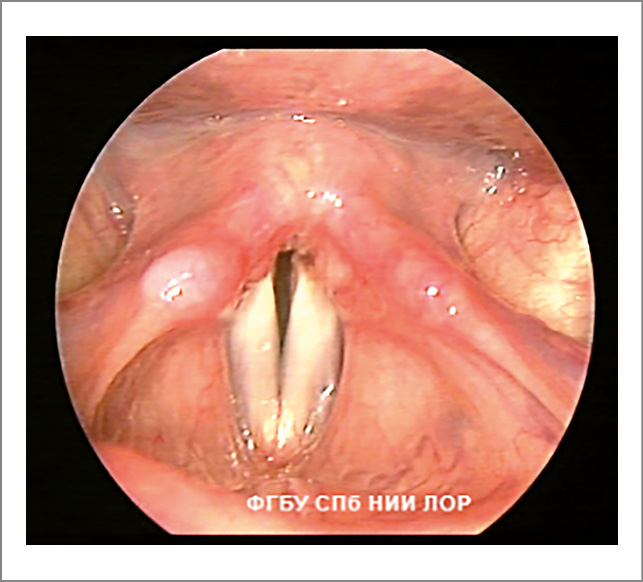

- Фонационная щель пациентов с функциональной дисфонией не соответствует форме фонационной щели здоровых людей. Изменение формы фонационной щели – основной признак гипотонуса голосовых складок. Сниженный тонус мышц гортани проявляется овальной, широкой линейной или треугольной фонационной щелью. Если у пациентов с функциональной дисфонией форма фонационной щели напоминает овал, то это свидетельствует о преимущественном снижении тонуса голосовых мышц (рис. 1). При снижении тонуса межчерпаловидных мышц фонационная щель имеет вид треугольника с верхушкой в передней комиссуре и основанием в межчерпаловидной области (рис. 2).

Рис. 2. Функциональная дисфония по гипотонусному типу (фонация): треугольная щель.